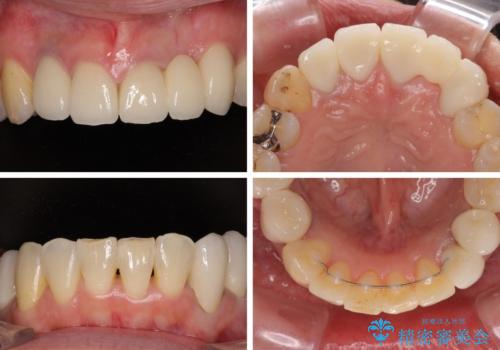

前歯の横幅が大きいことも気になっていたので、矯正治療で前歯5本の幅をコントロールしながら移動させ、治療開始前より一回りサイズの小さいセラミッククラウンを装着することができました。

矯正治療によって前歯にスペースを作り、左右対称となるようにオールセラミッククラウンにて補綴治療を行うとしました。

他にも奥歯の咬み合わせに問題があったので、全顎的な矯正治療を行い、前歯以外にも口を開けたときに目立つ奥の銀歯をセラミッククラウンにて補綴治療を行うこととしました。